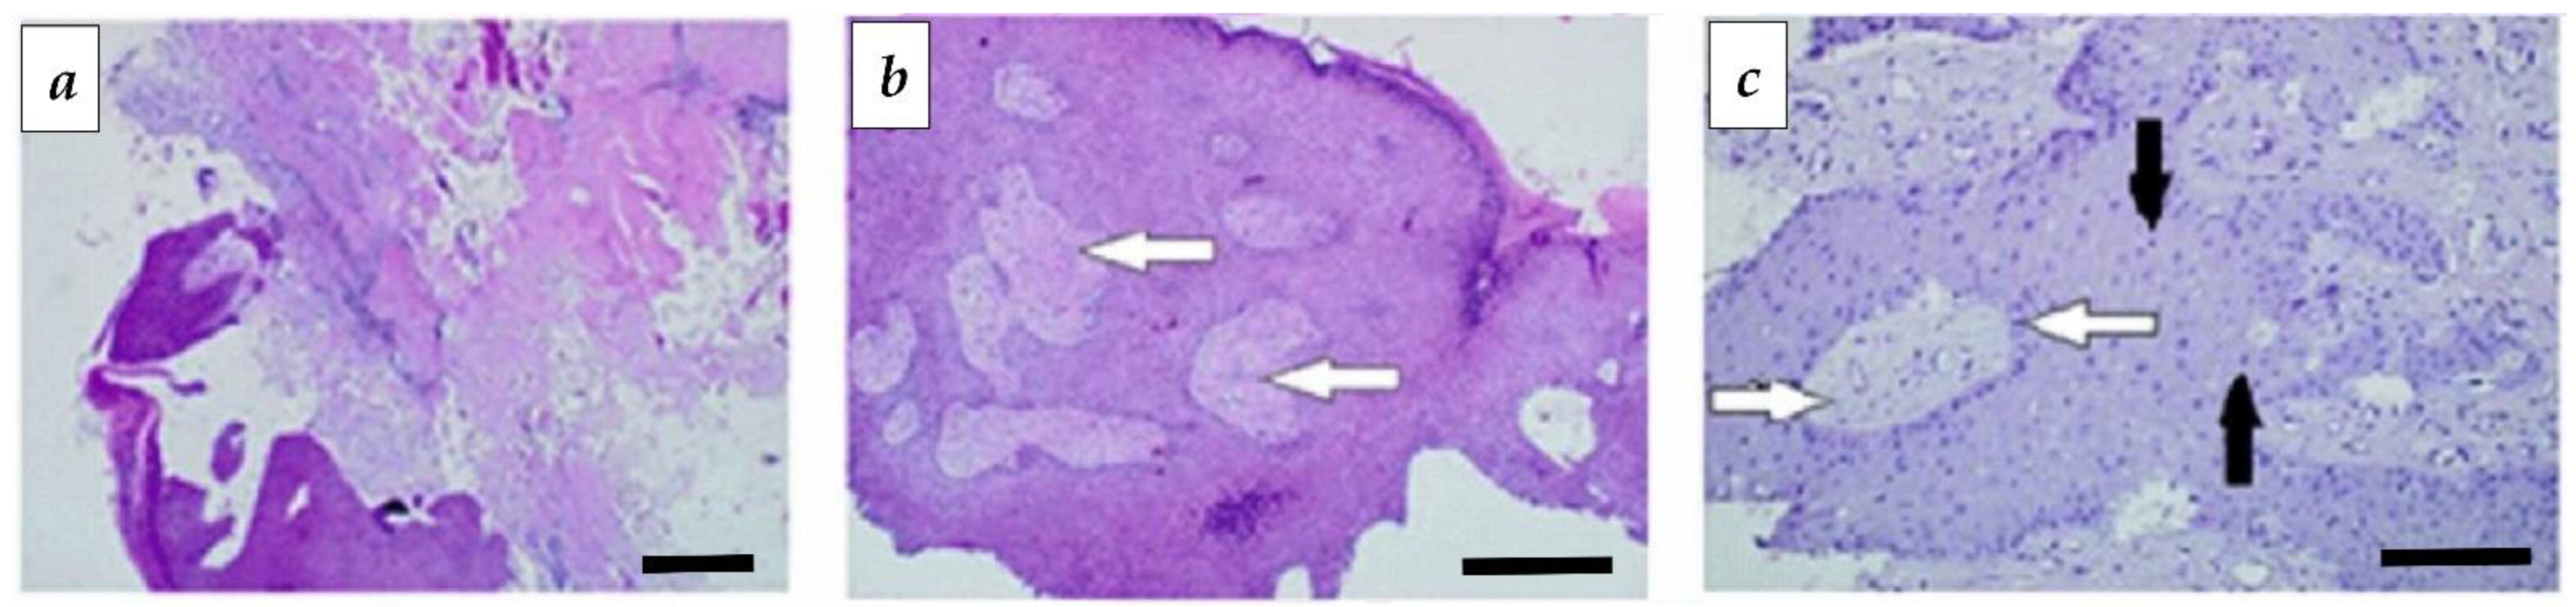

3.4. Immunohistochemical Analysis